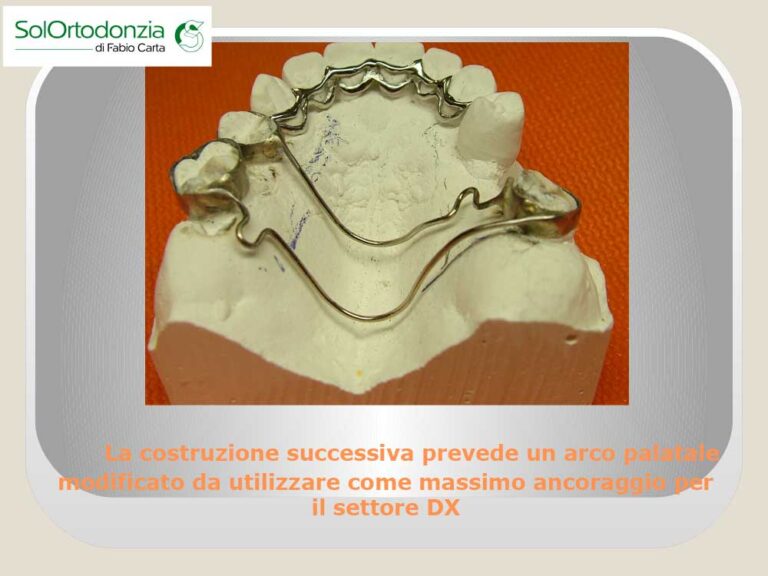

- Ortodonzia funzionale

- Ortodonzia fissa